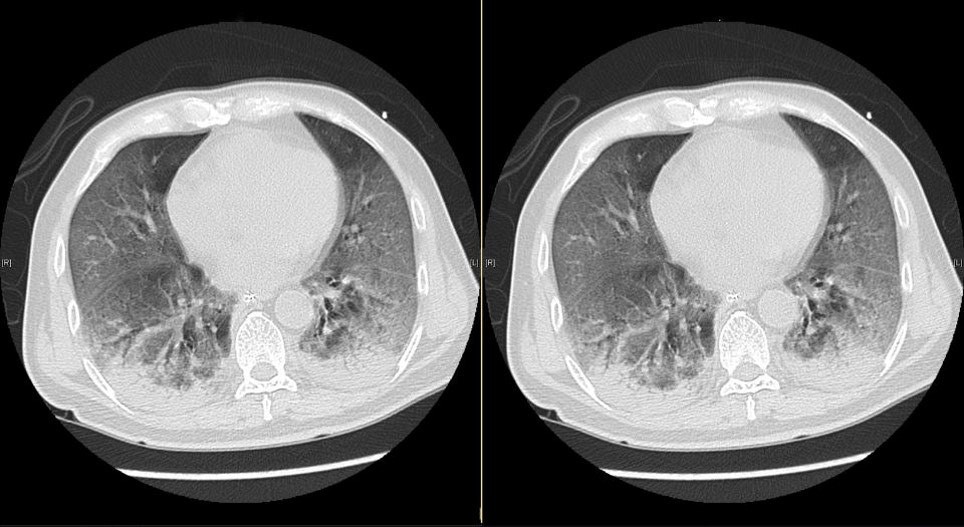

▲新冠肺炎患者肺部電腦掃描影像。(圖/香港醫管局,下同)

▲確診新型肺炎病人的肺部X光結果顯示,雙肺呈花白、混濁,主要在肺部的外圍,胸腔無積水。(圖/香港醫管局)